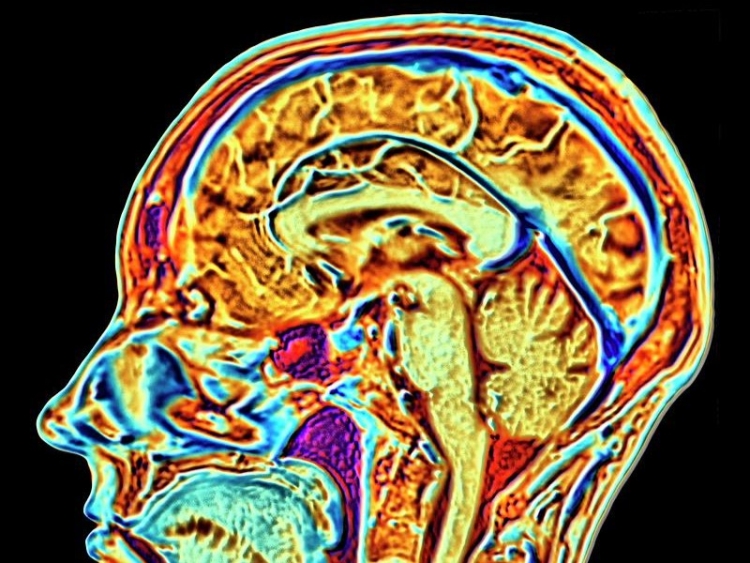

A new artificial intelligence (AI) is capable of spotting mental health conditions by sifting through brain imaging data to find patterns linked to autism, schizophrenia and Alzheimer’s.

The AI was trained on a massive dataset of more than 10,000 people to understand functional magnetic resonance imaging (fMRI), which measures brain activity by detecting changes with blood flow.

Once the AI could read basic fMRI, the team then fed it datasets of more than 1,200 people who have been diagnosed with mental illnesses – autism, schizophrenia and Alzheimer’s.